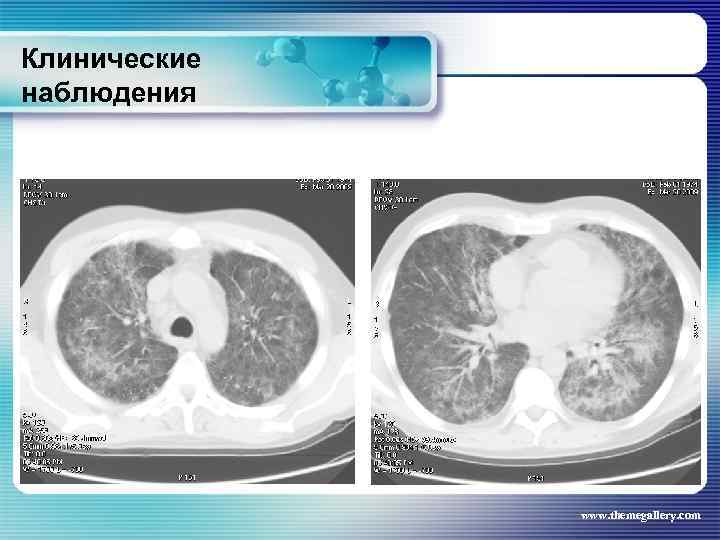

Клинические наблюдения Больной В. , 1974 г. р. Клинический диагноз: лимфома Ходжкина, нодулярный склероз IV В стадия с поражением подчелюстных, шейных, надключичных, подмышечных, паховых, абдоминальных, внутригрудных лимфатических узлов, легких, нижнегрудного и поясничного отделов позвоночника, костного мозга Проведено 8 циклов ВЕАСОРР, последний осложнился развитием тяжелого цитостатического пульмонита www. themegallery. com

Клинические наблюдения Больной В. , 1974 г. р. Клинический диагноз: лимфома Ходжкина, нодулярный склероз IV В стадия с поражением подчелюстных, шейных, надключичных, подмышечных, паховых, абдоминальных, внутригрудных лимфатических узлов, легких, нижнегрудного и поясничного отделов позвоночника, костного мозга Проведено 8 циклов ВЕАСОРР, последний осложнился развитием тяжелого цитостатического пульмонита www. themegallery. com